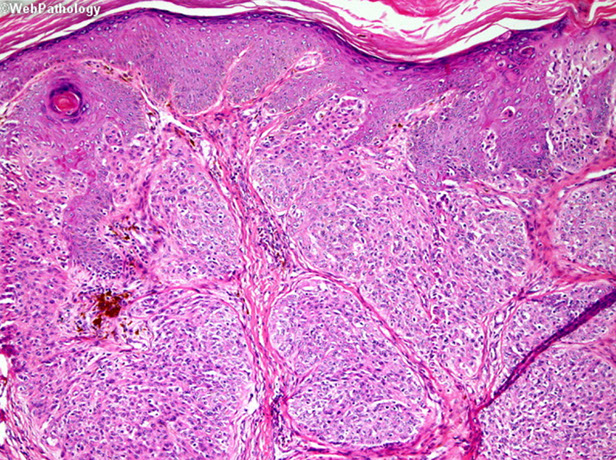

Trichoepithelioma

A type of trichoblastoma, also with basal cell appearance (basaloid cells c peripheral paslisading), concentric fibroblast-rich stroma, mucin only in tumor islands (not stroma), papillary mesenchymal bodies (PMB)

- multiple familial trichoepitheliomas (epithelioma adenoides cysticum) may have AD inheritance, CYLD (cylindromatosis) gene on cr 16q12-q13

- present as several small skin-colored papules in nasolabial folds

Brooke-Spiegler syndrome - numerous trichoepitheliomas and cylindromas

Rombo syndrome - trichoepitheliomas, milia, hypertrichosis, BCC, atrophoderma, vasodilation and cyanosis

Micro: May see horn cysts, calcifications, clefts bwt onion-skin collagen fibers in stroma

- finger-like projections with Swiss-cheese cribriform nodules

- stroma has the appearance of normal fibrous sheath of hair follicle (stroma is more cellular than in BCC)

IHC: (+) CD34 (in stroma), BCL-2 (at periphery of islands), CK20 Merkel cells (in tumor islands), BCC stains Ber-Ep4 diffusely

- PHLDA1 positive in BCC and not tricoeps